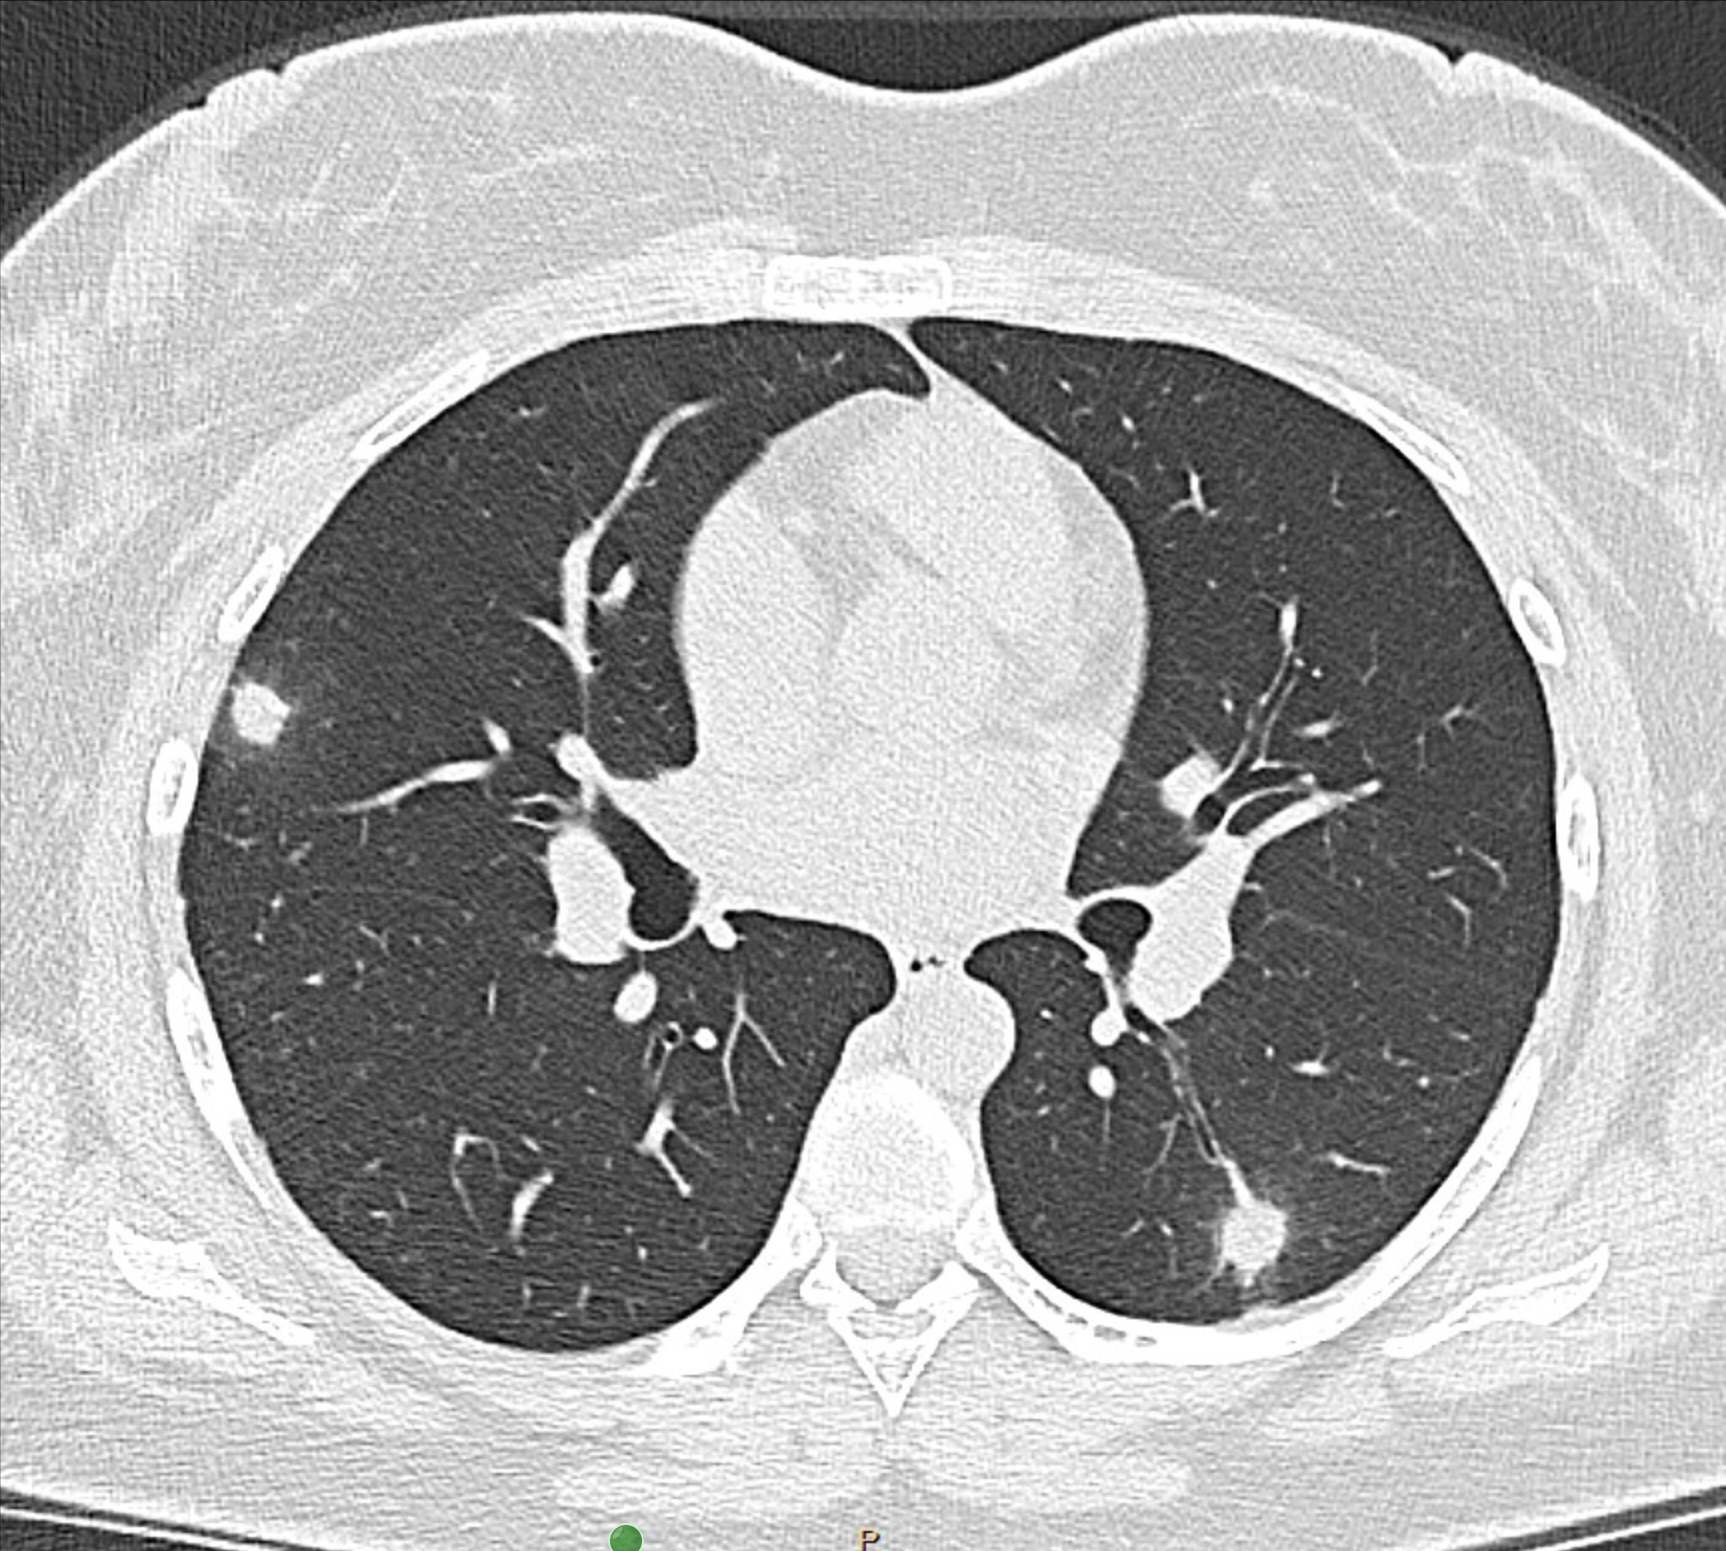

My name is Hafiza and I am a 20-year-old community organizer in NYC suffering from chronic & terminal complications of post-acute sequelae of SARS-CoV-2. In September 2024, I became sick with SARS-CoV-2 after returning from my 19th birthday trip. Since, I have developed Interstitial Lung Disease (specifically, a rare kind called chronic hypersensitivity pneumonitis), Long COVID/PASC, ME/CFS, Dysautonomia/POTS, in addition to a myriad of debilitating neurological symptoms I am undergoing treatment for including cognitive impairment, memory loss and seizures. My cHP is driven by my hypersensitivity to unidentifiable environmental antigens; in simple terms, I am deadly hypersensitive to the environment and continuous exposure (primarily all outdoors but also indoors) will progressively worsen my disease prognosis. Due to this, my quality of life has drastically reduced as I have become more isolated from the outside world and am left housebound. Even with a high quality respirator, going outside leaves me bedbound with intense lung pain and damage. As a young disabled patient with ILD, there is no quality of life for me without my bare necessities and survival met. Due to financial distress, I am reconsidering if a lung transplant is a viable future for me should candidacy be granted with disease progression, as an extension of life comes with more financial obligations that I do not have the stability and safety for. Since September 2024, I have become a full-time patient with 75+ appointments from my onset 13 months ago, a care team of 15+ specialists, at least 5-15 doctor appointments a month, in addition to managing my chronic pain and treatment regimen alone. I require care, assistance, and accompaniment from my roommate and friends for day-to-day routine tasks and errands, otherwise effortless pre-pandemic and pre-disability.

Before I developed chronic & terminal illness from SARS-CoV-2, I had a very fulfilling social life as any other young adult. I was a full-time scholarship student at NYU. I enjoyed traveling, reading, writing, cooking, spending time in community organizing spaces and quality time outdoors which wasn’t afforded to me during my upbringing. Like many other poor / working-class scholarship students, I have been financially independent from a young age and spent years laboring tirelessly to provide for myself. This past summer, when my lungs worsened, I had no choice but to part ways with my career and academic life, in addition to all of my hobbies and interests. Only weeks before my 20th birthday this past August, I underwent a risky lung procedure unsure if I’d make it out alive, which led to the final diagnosis of chronic hypersensitivity pneumonitis. Previously, I have seen several doctors that have brushed off my lung condition as asthma since my onset due to young age; one year later, after building a competent care team of specialists, I finally received an answer but it was only the beginning of an excruciating & long medical / financial journey. My life has completely altered since my diagnosis as I navigate a complex and cruel healthcare system, in addition to managing a complex disease without a support system.